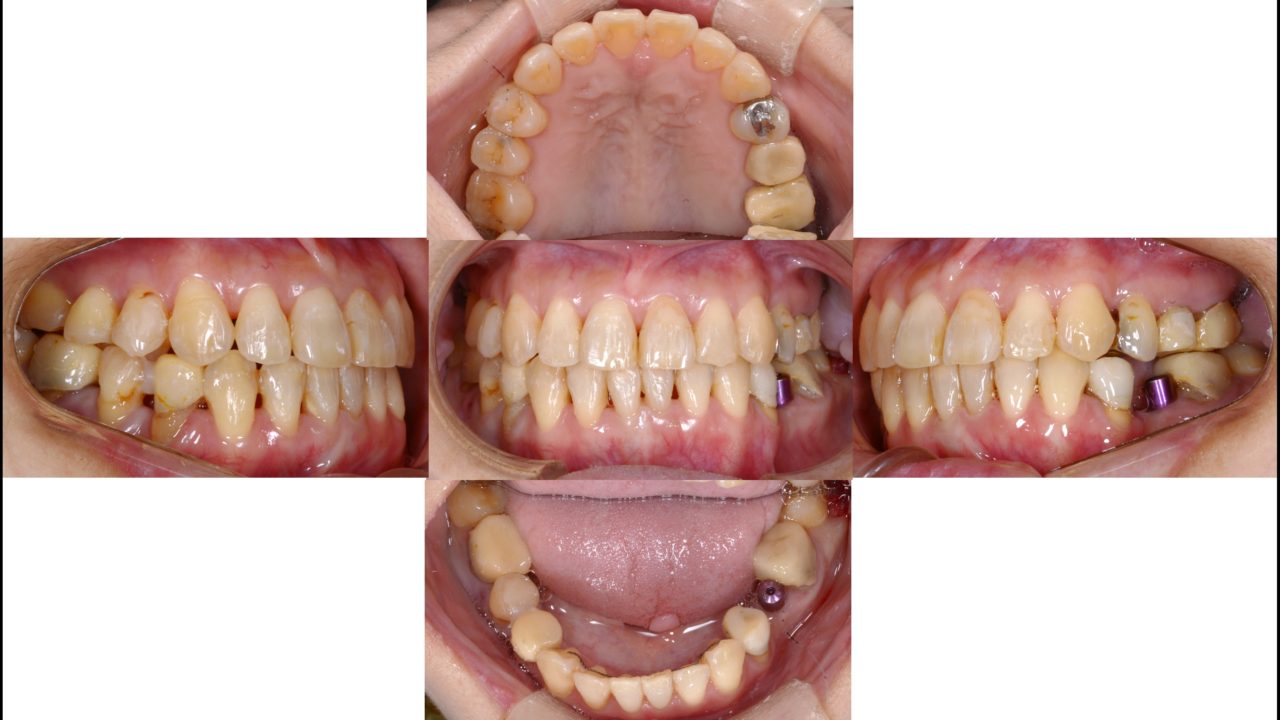

After

矯正治療終了 2020.4.20

補綴修復治療終了

インプラント2本を含むセラミック治療終了